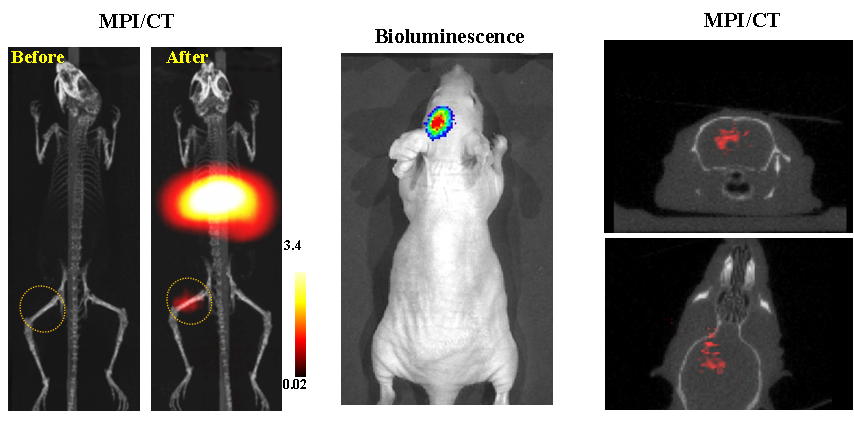

今年二月份,宋国胜教授与斯坦福大学饶江宏教授合作,通过系统的研究获得了影响磁性粒子成像信号的作用规律和关键原理,开发了新型磁性粒子探针---FeCo合金粒子,并首次应用于磁性粒子成像(MPI)。该造影剂在极低含量时(5 ng)仍具有很强的造影效果。这意味着,未来在进行人体成像时,可以使用更小剂量的造影剂,从而避免高剂量造影剂引起的肾肝损伤。基于MPI的直接成像原理,我们可以对造影剂进行正相和无背景干扰的活体成像,极大地提高信噪比。这项技术为肿瘤早期诊断、癌细胞示踪、脑中风、药物输送治疗、肺部灌注成像、胃肠出血、神经退行性疾病、磁热治疗等在活体中的可视化研究,提供了强有力的手段。相关研究成果以全彩H漫

为第一单位发表在Nature 子刊《Nature Biomedical Engineering》。该期刊是“生物医学工程”的顶级期刊。宋国胜教授为该论文的共同通讯作者。